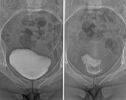

Bekken |

Cystografie |